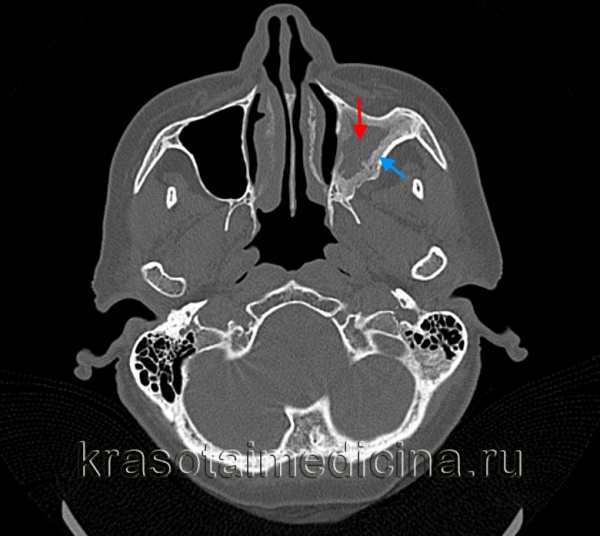

Диагностические методы выявления острого гайморита согласно МКБ-10

Диагноз «острый гайморит» ставится на основании осмотра, риноскопии и жалоб пациента. Опытный доктор сразу скажет, что вы «владелец» гайморита. Для подтверждения диагноза могут быть назначены дополнительные методы диагностики:

- рентгенография верхнечелюстного синуса;

- обзорная рентгенография околоносовых пазух;

- КТ и МРТ;